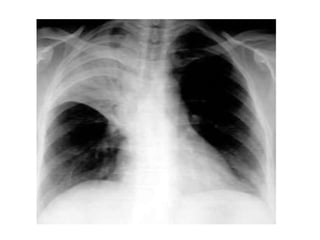

Condensación basal izquierda retrocardíaca

NEUMONIA ATIPICA (legionella)

NEUMONIA ATIPICA (M. Pneumonae)

NEUMONIA ATIPICA (C. Pneumonae)